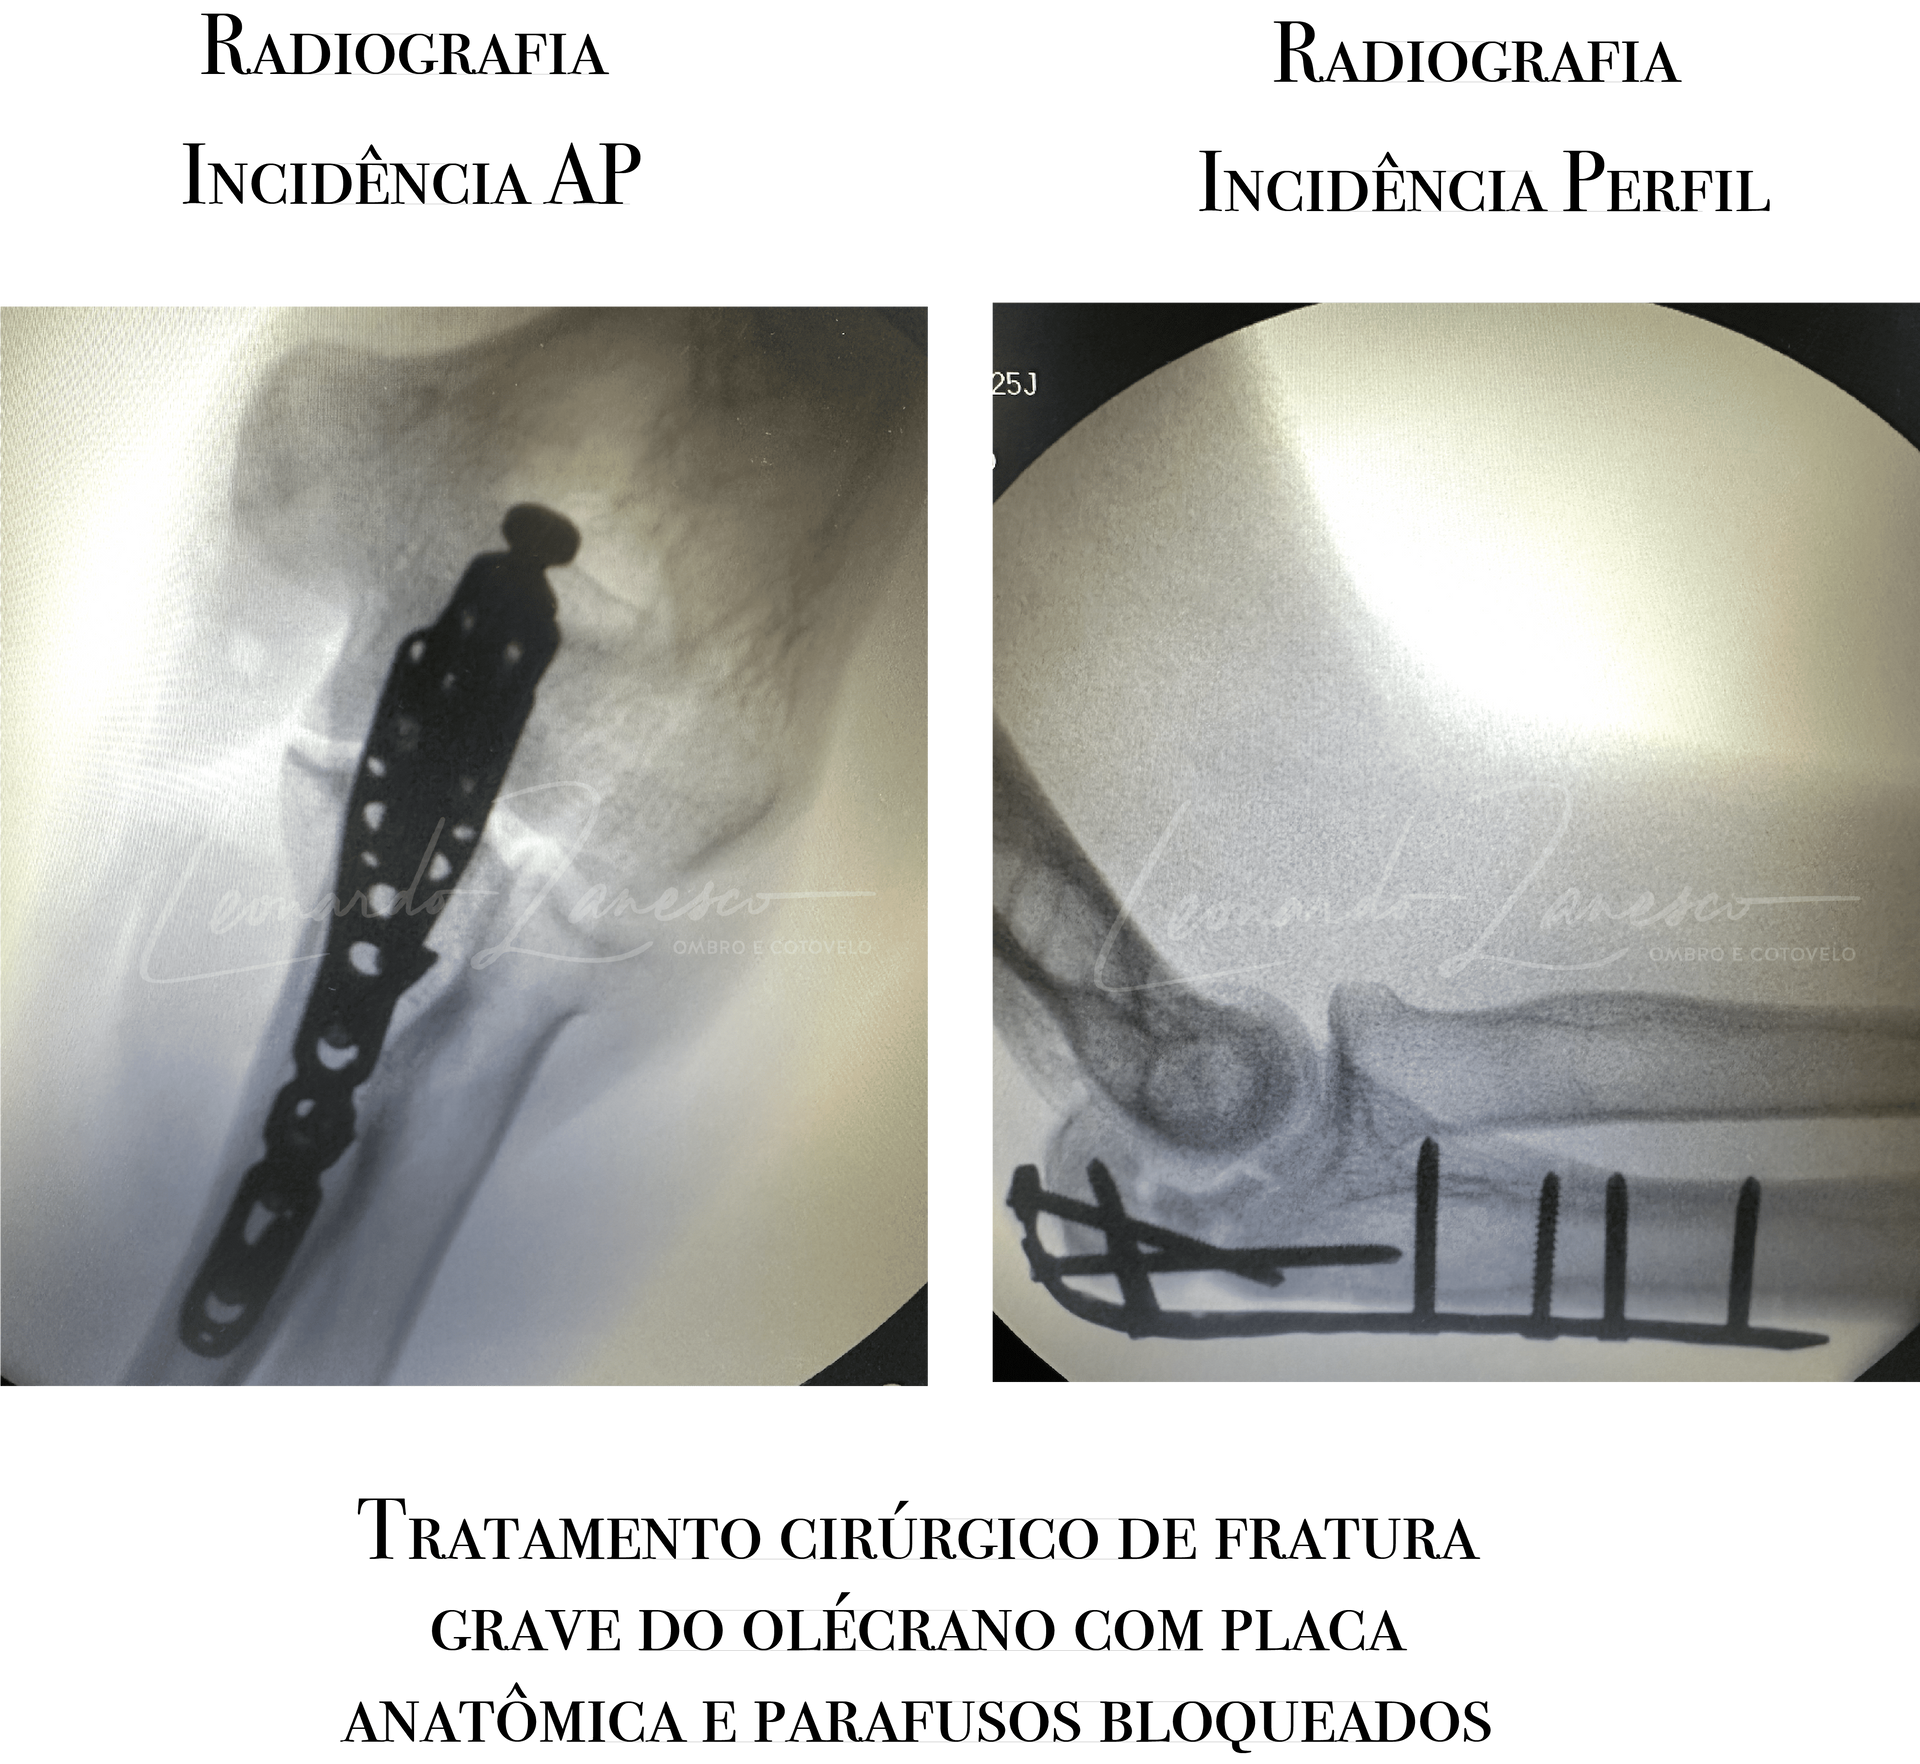

Reconstrução com placa e parafuso (ORIF):

É a técnica

mais versátil, indicada especialmente nas fraturas com

cominuição e/ou

instabilidade (incluindo transolecranon e extensões para o corpo da ulna). As placas pré-contornadas de ângulo fixo e baixo perfil, mais atuais, possibilitam uma taxa menor de complicações de cicatrização e menor desconforto no pós-operatório.